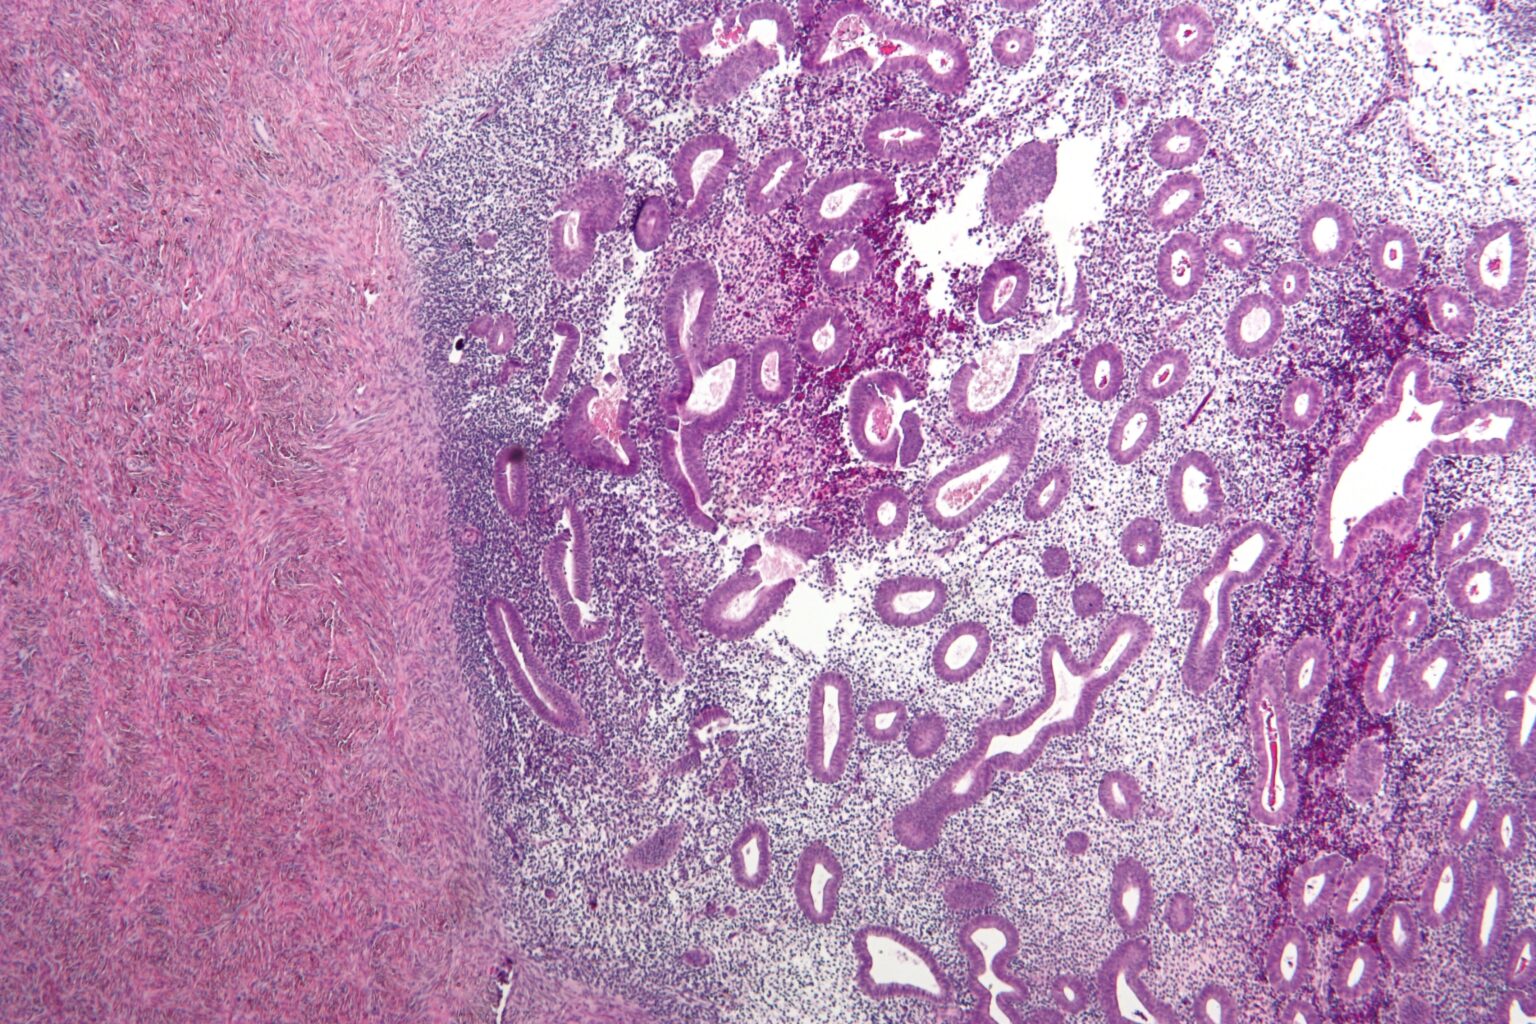

Endométriose - la science tente enfin de rattraper le retard @wikipedia commons